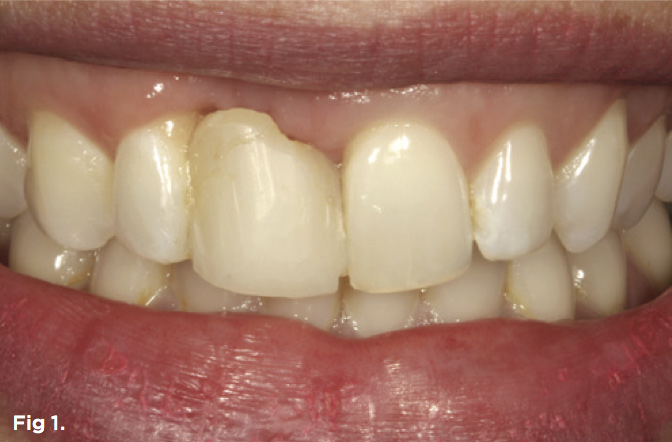

A 38-year-old Caucasian female patient presented with a high smile line and loss of the papilla between tooth No. 7 and edentulous adjacent site No. 8 (Figure 1). Understandably, the patient was unhappy and embarrassed about her esthetic condition. Her dental history revealed tooth replacement of No. 8 with an implant that eventually failed. The site had been previously bone grafted upon implant removal. She was given a composite pontic No. 8 bonded to a tooth No. 7 composite veneer as a transitional restoration. The implant was positioned too close to the proximal surface of tooth No. 7, which stripped the periodontal attachment of the root and ultimately caused loss of the papilla (Figure 2). As previously outlined, the treatment sequence would be to first provide a provisional restorative solution to evaluate the projected outcomes and assess if the patient was willing to undergo orthodontic therapy. In this situation, a full-coverage crown No. 7 with a cantilevered pontic No. 8, with artificial acrylic gingiva to replace the lost papilla on the mesial aspect of tooth No. 7 was used as a transitional temporary prosthesis (Figure 3). In addition, a composite resin restoration was placed on the mesial aspect of tooth No. 9 to restore its individual tooth proportion and shape. The patient’s esthetic outcome could now be evaluated with restorative correction alone; it was therefore mutually determined that the correction of her deformity would best be served with additional orthodontic forced eruption therapy. A fixed orthodontic appliance (brackets) was bonded to the teeth and temporary prosthesis. The level of the interproximal pink acrylic was used as a therapeutic guide for the amount of forced eruption required as well as the alignment of the mesial papilla of No. 7 to that of the adjacent papillae height (Figure 4). Floss was used to elevate the amount of vertical movement achieved relative to the adjacent papilla tooth No. 9. Eventually, all the artificial pink acrylic was removed. (Note that the distal papilla on tooth No. 7 also comes more incisal—in fact, it is slightly excessive at the endpoint of treatment [Figure 5]). However, the distal papilla and midfacial tissues of tooth No. 7 can be reshaped through clinical crown lengthening toward the end of treatment prior to definitive restoration, thereby restoring the proper papilla height-to-tooth ratio of 40%. After stabilization of tooth No. 7 for a minimum of 6 months post-orthodontics, an implant was placed in site No. 8. A papilla-sparing incision design was used for flap elevation (Figure 6), bone allograft was used to further augment the facial aspect of the ridge simultaneously with implant placement (Figure 7), and a resorbable membrane was used for guided bone regeneration.

Fig 1. Preoperative extraoral view of patient with significant loss of the papilla on the mesial aspect of tooth No. 7 and a high smile line.

Figure 1